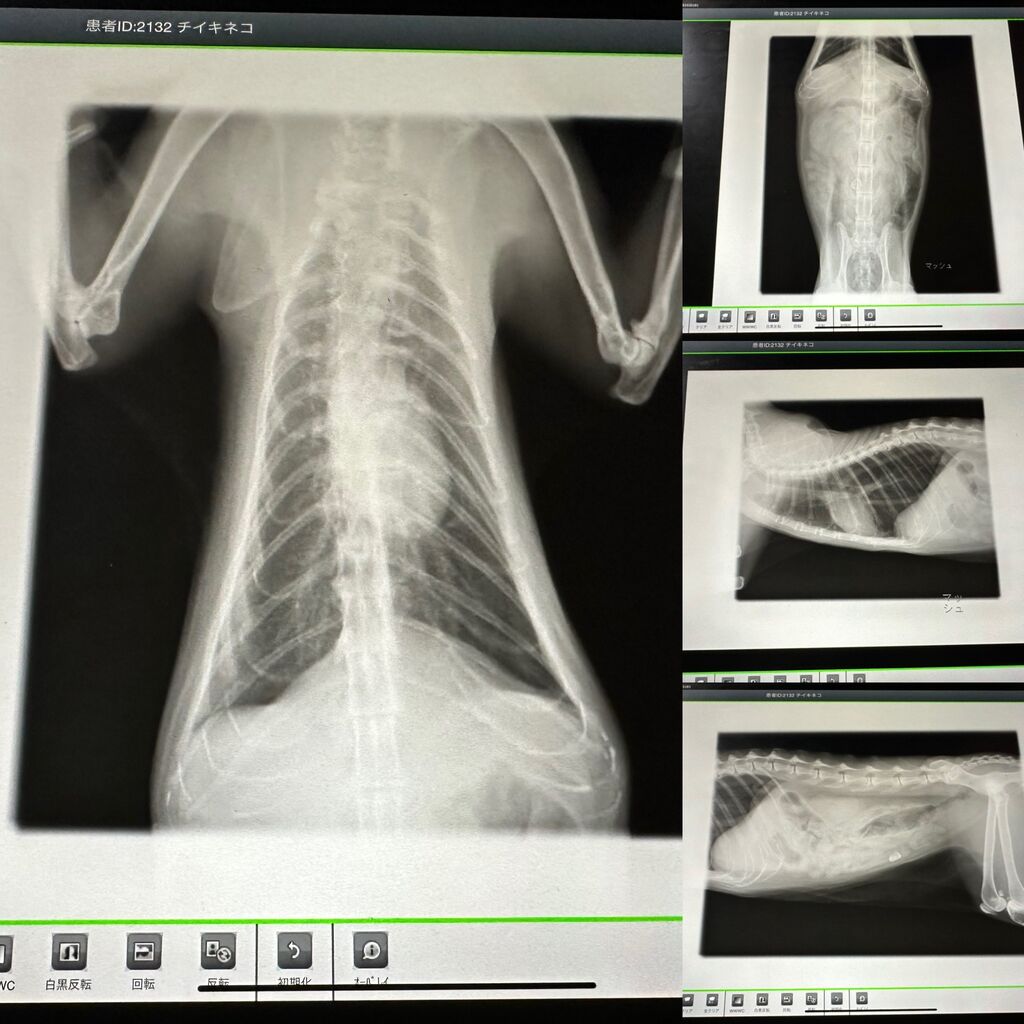

レントゲンや超音波検査もやりました

▼レントゲン

先生いわく、特に異常はないそうです